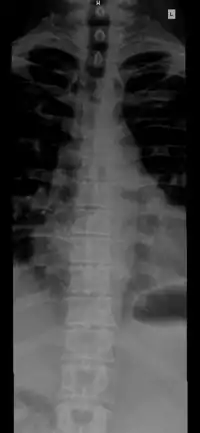

Structure

The number of vertebrae in a region can vary but overall the number remains the same. In a human vertebral column, there are normally 33 vertebrae.[3] The upper 24 pre-sacral vertebrae are articulating and separated from each other by intervertebral discs, and the lower nine are fused in adults, five in the sacrum and four in the coccyx, or tailbone. The articulating vertebrae are named according to their region of the spine. There are 7 cervical vertebrae, 12 thoracic vertebrae and 5 lumbar vertebrae. The number of those in the cervical region, however, is only rarely changed,[4] while that in the coccygeal region varies most.[5] One study of 908 human adults found 43 individuals with 23 pre-sacral vertebrae (4.7%), 826 individuals with 24 pre-sacral vertebrae (91%), and 39 with 25 pre-sacral vertebrae (4.3%).[6]

The vertebrae in the human vertebral column is divided into different regions, which correspond to the curves of the vertebral column. The articulating vertebrae are named according to their region of the spine. Vertebrae in these regions are essentially alike, with minor variation. These regions are called the cervical spine, thoracic spine, lumbar spine, sacrum, and coccyx. There are seven cervical vertebrae, twelve thoracic vertebrae, and five lumbar vertebrae.

The number of vertebrae in a region can vary but overall the number remains the same. The number of those in the cervical region, however, is only rarely changed.[4] The vertebrae of the cervical, thoracic, and lumbar spines are independent bones and generally quite similar. The vertebrae of the sacrum and coccyx are usually fused and unable to move independently. Two special vertebrae are the atlas and axis, on which the head rests.

Individual vertebrae are named according to their region and position. From top to bottom, the vertebrae are:

- Cervical spine: 7 vertebrae (C1–C7)

- Thoracic spine: 12 vertebrae (T1–T12)

- Lumbar spine: 5 vertebrae (L1–L5)

- Sacrum: 5 (fused) vertebrae (S1–S5)

- Coccyx: 4 (3–5) (fused) vertebrae (Tailbone)